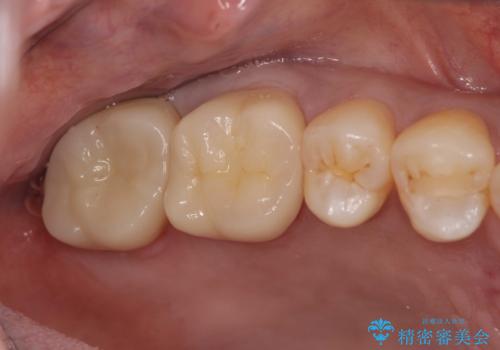

目立つ銀歯が口腔内から取り除かれ、ジルコニアクラウンによる白い歯へと置き換わったことで自信を持って笑えるようになったとの言葉をいただきました。

- 33万円(仮歯・ジルコニアクラウン×3)費用は治療当時の料金となります